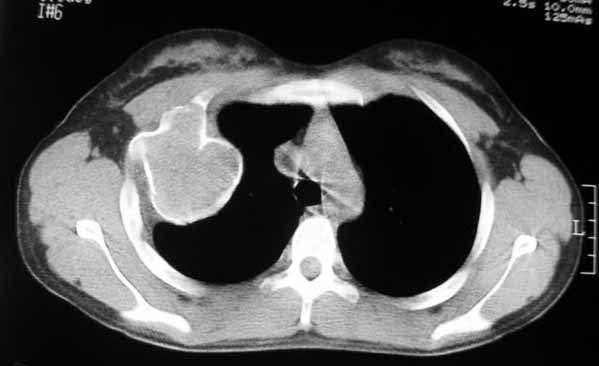

以下是引用dyqct在2007-5-26 12:01:00的发言:[br]右第二肋腋侧呈明显膨胀性、分叶状改变,内无明显间隔,ct值49hu,病变大小约67x57mm,周围硬化缘无断裂,内缘见多数骨嵴,肿块与正常骨间界限清楚。无移行带。周围软组织无浸蚀,胸膜腔无积液。[br]考虑:1、右第二肋动脉瘤样骨囊肿可能性大;[br] 2、需同骨巨细胞瘤、浆细胞瘤、骨纤鉴别。